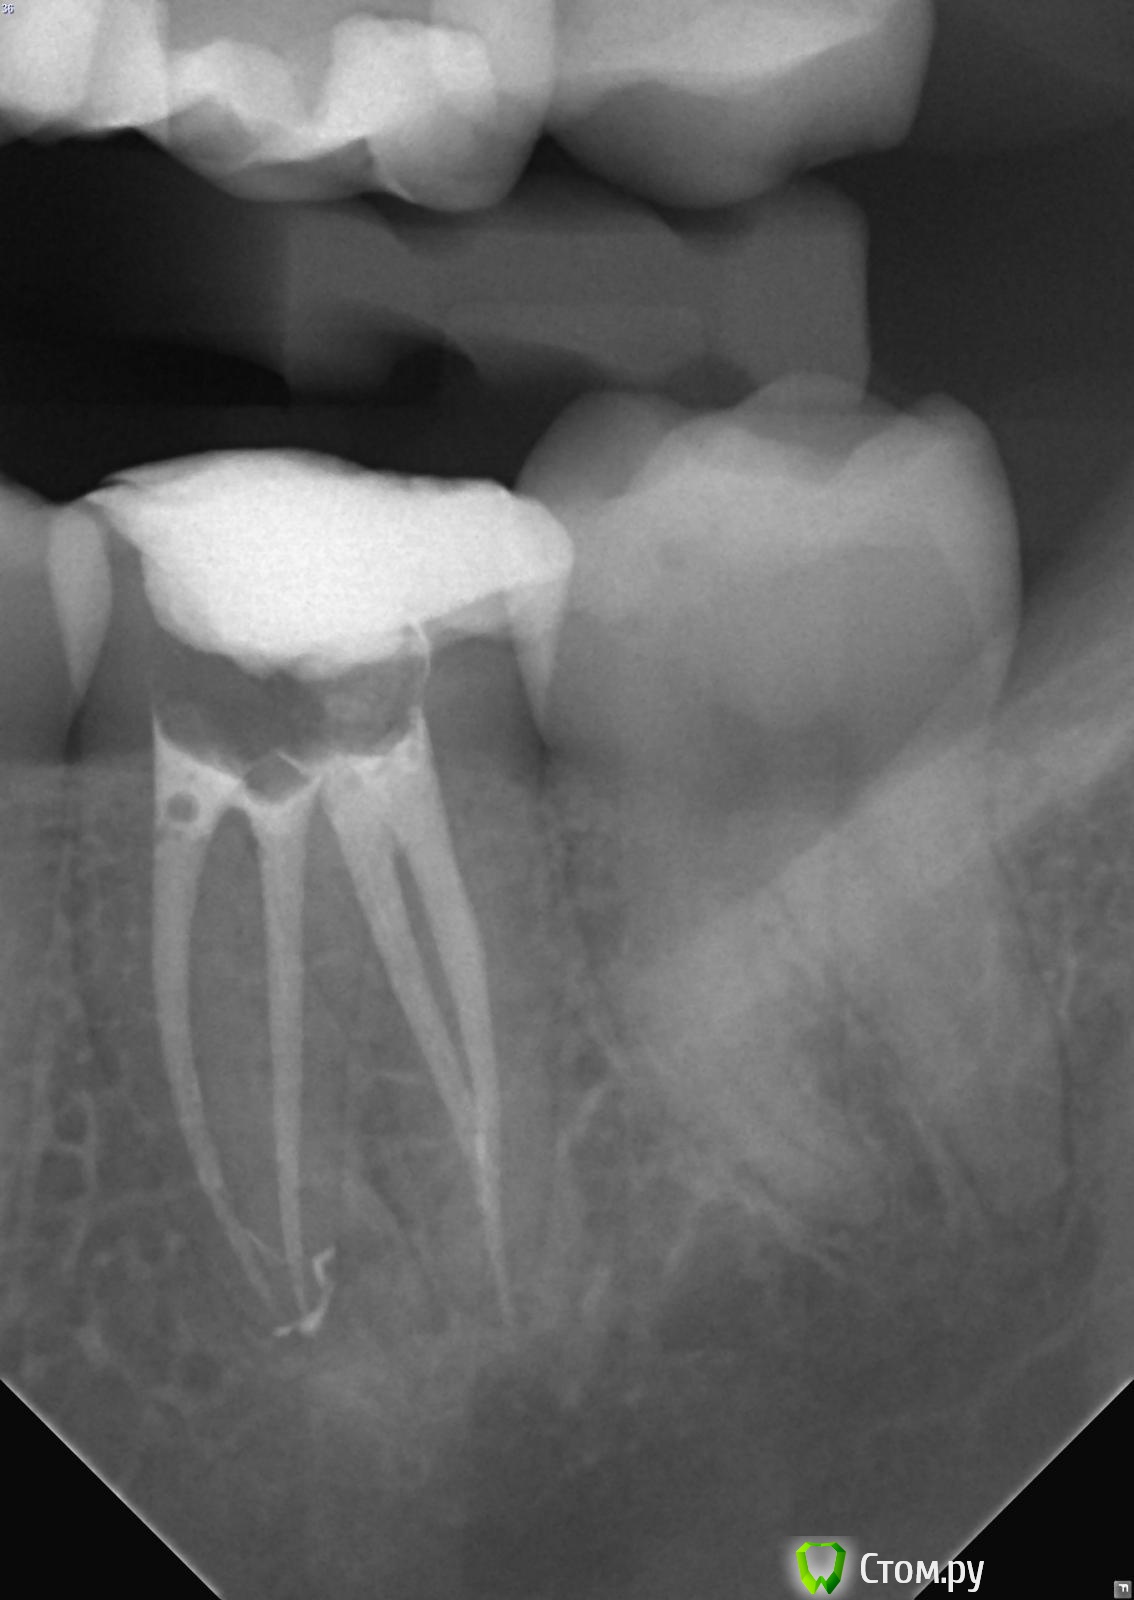

felicidade Опубликовано 23 июня, 2014 Поделиться Опубликовано 23 июня, 2014 (изменено) И снова добрый день Я хотела бы спросить, есть ли смысл в перелечивании каналов зуба №36 (девитализирован лет 10-12 назад), чтобы в будущем установить на корень литую культёвую вкладку и коронку? Каналы запломбированы жутко, под корнем есть киста, от самого зуба остались только стенки..Чисто физически, есть ли у него потенциал в плане дальнейшего протезирования, при условии, что перепломбировка каналов поможет, и киста чудесным образом уйдёт? Очень боюсь, что не выдержит жевательной нагрузки, что не на что попросту будет крепить протез.Врач-эндодонт в Любляне сначала подозревала резорбцию корня и оставленный в канале обломок иглы, но КТ показала, что ничего из этого нет. КТ я запросила у словенской клиники, в которой её делала, но пока на почту мне её не прислали, есть только такой снимок.Я, конечно, настроена на сохранение зуба, он меня никак не беспокоил все эти долгие годы (ТТТ), но хочу понять, стоит мне тратить 700 евро на эндо, или, может, лучше сразу удалять? Спасибо большое заранее p.s.Рентген сомнительного двадцать пятого зуба с неизвестным количеством корней/каналов смогу сделать и выложить только в середине июля в Любляне, т.к. тут в Италии рентген-снимки и КТ делаются строго по направлению врача. Изменено 23 июня, 2014 пользователем felicidade Ссылка на комментарий

felicidade Опубликовано 23 июня, 2014 Автор Поделиться Опубликовано 23 июня, 2014 ИванК, спасибо за ответ! Затеплилась надежда Откопала ещё два снимка, где частично виден зуб №36 (первый снимок уж больно плохого качества, эти получше, хоть и не целиком показывают зуб). Ссылка на комментарий

DokDent Опубликовано 23 июня, 2014 Поделиться Опубликовано 23 июня, 2014 Вот ещё один снимок с Вашей панорамки. Теоретически можно перелечить и восстановить, но это 2-мерное изображение, поэтому по нему трудно судить об истинной картине что с корнями и вокруг них. Всё же лучше перед вмешательством посмотреть на кт. 1 Ссылка на комментарий